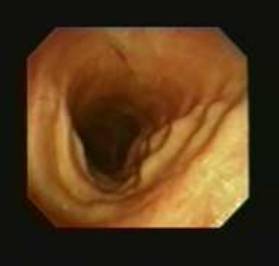

20 下面图中的解剖结构是

A. 成人呼吸道最狭窄的部分

B. 儿童呼吸道最狭窄的部分

C. 成人女性呼吸道最狭窄的部分

D. 成人男性呼吸道最狭窄的部分

20B

环状软骨是儿童呼吸道最窄的一部分而声门是成人呼吸道最窄的部分。如果对一个儿童进行支气管镜检查,记得会厌和喉通常更前,气管更柔软、容易弯曲,口咽部组织和粘膜更柔软易损伤,这些是很重要的 如果必须插管,无接头的气管插管应该用在8岁以下的儿童。气管插管外径应该近似于儿童鼻孔的大小。多数的急诊室均具有Broeslow卷尺更好的测量。